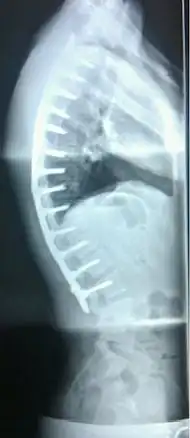

| Scheuermann's disease on lateral Xray of the T spine | |

In severe or extreme cases, patients may be treated through an extensive surgical procedure in an effort to prevent the disease from worsening or harming the body. The skeletal deformity caused by Scheuermann's disease can be corrected or partially corrected with surgical procedures, almost all of which include multi-level spinal fusion and hardware instrumentation, i.e., rods, pedicle screws, etc. It is important to realize the surgery aims to reduce pain, and not cosmetic defect. As always, surgical intervention should be used as a last resort once conservative treatment fails or the patient's health is in imminent danger as any surgical procedure is not without risk. However, the chances of complication are relatively low, and the surgeries are often successful.

The classic surgical procedure entails entering two titanium rods, each roughly 1.5 feet (0.46 m) long (depending on the size of the kyphosis) into the back on either side of the spine. Eight titanium screws and hardware are drilled through the bone to secure the rods onto either side of the spine. On the internal-facing side of the spine, ligaments (which can be too short, pulling the spine into its abnormal shape) must be surgically cut or released, not only stopping part of the cause of the kyphosis, but also allowing the titanium rods to pull the spine into a more natural position. The damaged discs between the troubled vertebrae (wedged vertebrae) are normally removed and replaced with bone grafting from the hip or other parts of the vertebrae, which once healed or "fused" will solidify. The titanium instrumentation holds everything in place during healing. The patient can expect to remain in hospital for a minimum of a week, and possibly longer. They may then be required to wear a brace for several months more to ensure the spine heals appropriately. The titanium instrumentation may stay in the body permanently, or be removed years later. Patients who have undergone such surgery may need physical therapy to manage pain and mobility. Recovery can be prolonged: typically patients are not allowed to lift anything above 5–10 pounds (2.3–4.5 kg) for 6 months to 1 year, and many are out of work for 3 to 6 months. However, once the fusion is solidified, most patients can return to their usual lifestyle within 1–2 years.